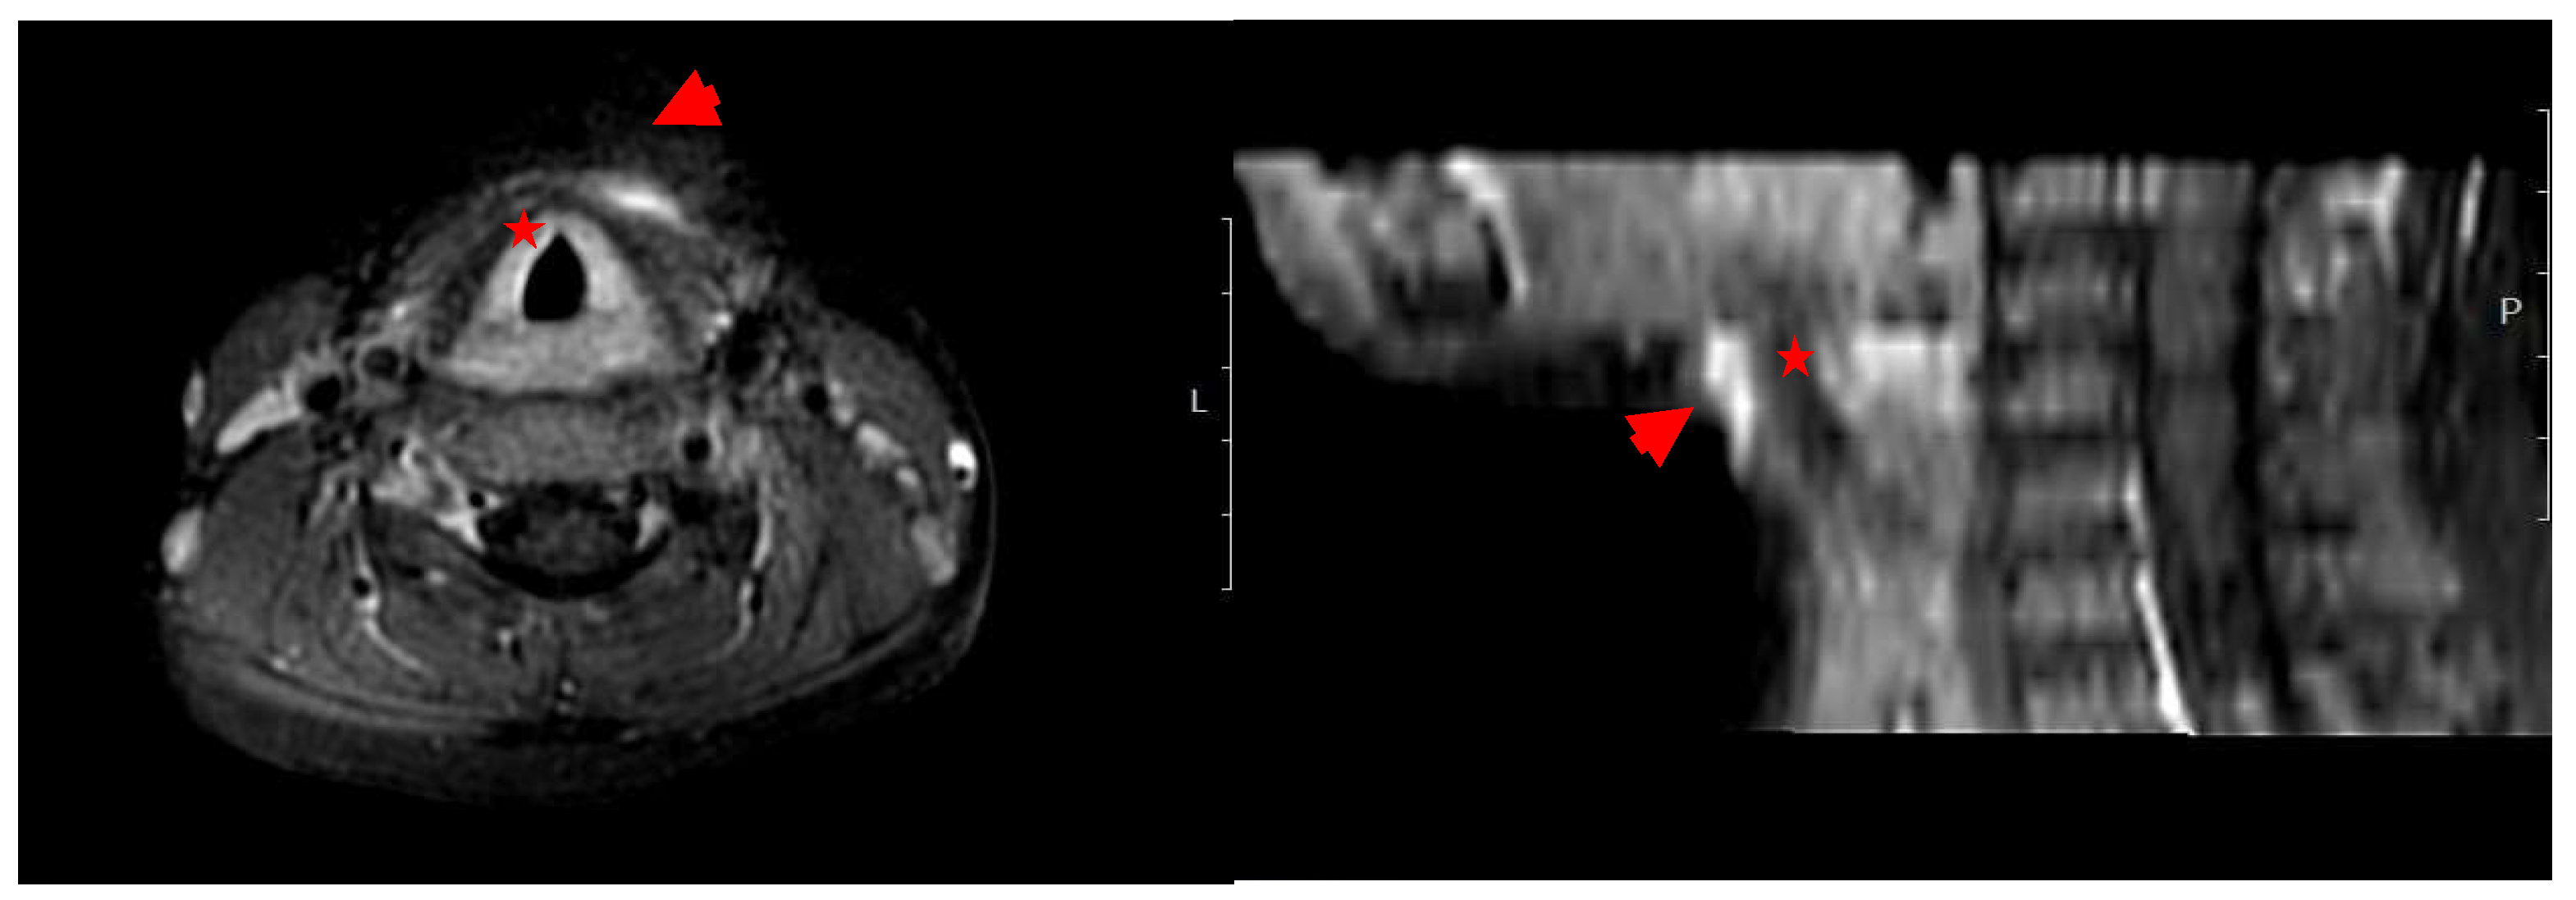

Both cases presented with fever and a localized swelling, each one in different body sites, with no neurological signs. Laboratory testing for Case-1 revealed leukocytosis (WBC 18,600/μL) and elevated CRP (58.3 mg/L) (Table 1). Imaging studies, including ultrasound and MRI of the neck, revealed a pathological finding: a linear contrast-enhancing lesion suggestive of a fistulous tract at the level of the hyoid bone, immediately left of the midline, with associated inflammation of the overlying subcutaneous tissue (Figure 1). The patient was diagnosed with a cervical abscess based on clinical and laboratory findings.

Figure 1.

Imaging (MRI). Case-1: Characteristics of the lesion in the cervical region. By the use of T2-weighted Magnetic Resonance. Axial (horizontal) view (left) and sagittal (side) view (right) of the neck. Hyperintense (bright) areas anterior to the trachea (red star) are indicated by red arrowheads suggesting a fluid collection or, abscess, or edematous tissue.